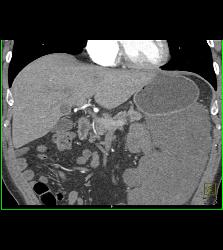

Diagnosis

GIST Tumor